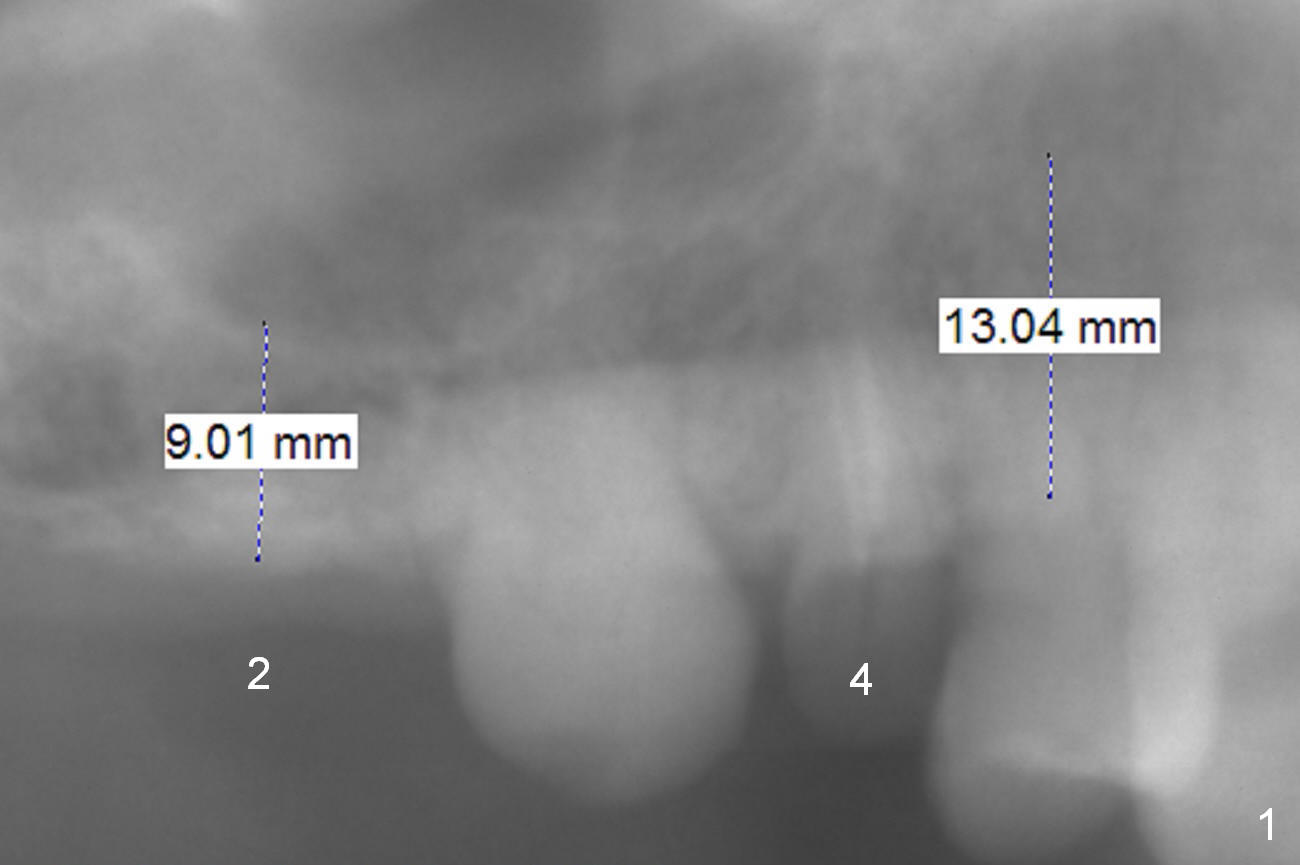

A 73-year-old man (HR) requests restoration at #2-4 (#3 lost crown).  To prevent buccal plate fracture associated with extraction at #4, the buccal portion of the root will be preserved (socket shield, surgical bur block) after buccal sulcus incision.  Still prepare proximators for extraction.  Granulation tissue is going to be removed, followed by Clindamycin.  Since there are two canals, start osteotomy using Magic Expander (ME) 3 mm in the palatal portion of the socket apex (oval) for 2 mm.  Insert a 4 or 4.5x11 mm dummy implant and take PA to determine placement level.  Osteotomy at #2 will begin with Magic split, followed by ME for 9 mm.  Use drills if bone density is high.  Sinus lift will be done at the sites.  An immediate splinted provisional will be fabricated by hand at #2-4.